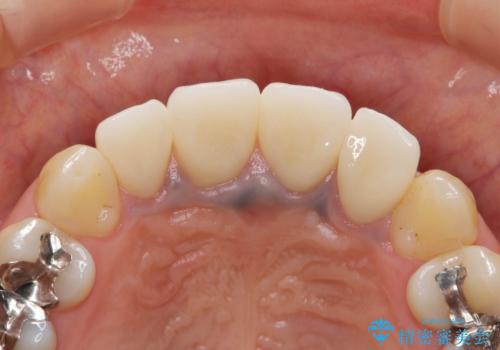

- 歯ぐきの黒っぽさ、暗い色調の前歯の改善を求めて来院されました。

金属を用いたコア・クラウンが装着されており、全ての金属を除去したのちのメタルフリー治療を計画します。

金属のフレームを用いるクラウンは色調が暗くなる傾向にありますが、セラミッククラウンに置き換えたことで自然な明るさ、審美性を取り戻すことができました。